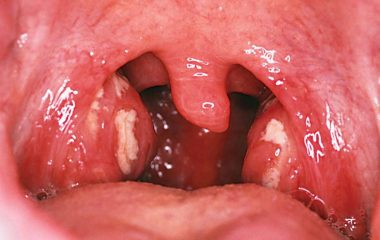

Хронический тонзиллит может обостряться во время беременности. Это заболевание требует комплексного лечения с применением нескольких средств.

Катаральная ангина является одной из самых распространенных форм тонзиллита. Лечение проводится различными препаратами.